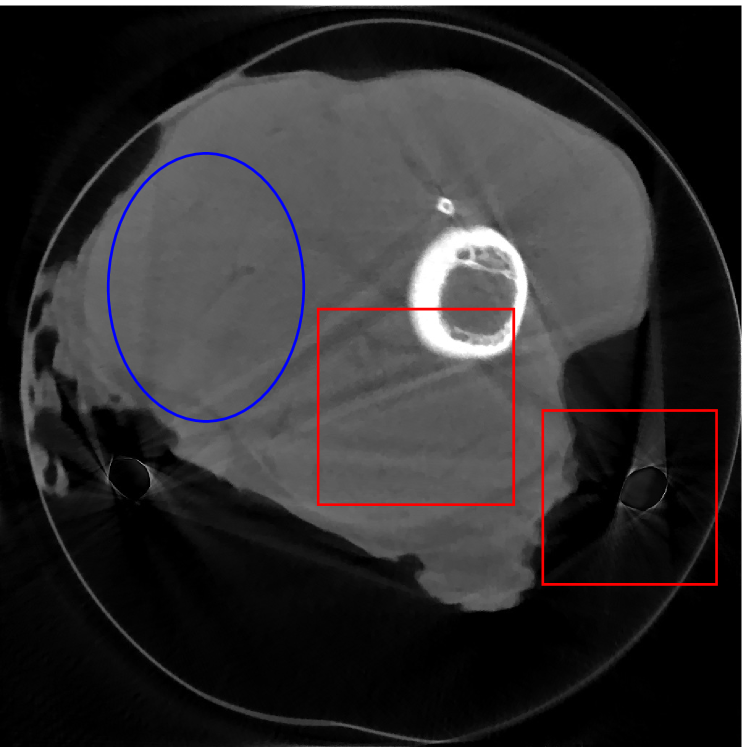

Figure 12 shows a comparison between the reconstructed image from NMAR and the unweighted JSR model. Figure 13 shows a comparison between the reconstructed images from TV-FADM and the proposed re-weighted JSR model. Zoom-in views are provided in both Figure 12 and Figure 13 for a better visual assessment. As one can see that the reconstructed images from the unweighted JSR model and TV-FADM are less noisy than NMAR as indicated by the blue ellipse curve, whereas NMAR does a better job in preserving image features and suppressing metal artifacts. However, there are also new artifacts around the metal on the right as shown in Figure 12(d). The proposed re-weighted JSR model has best overall performance in terms of feature preservation, noise and metal artifact reduction.